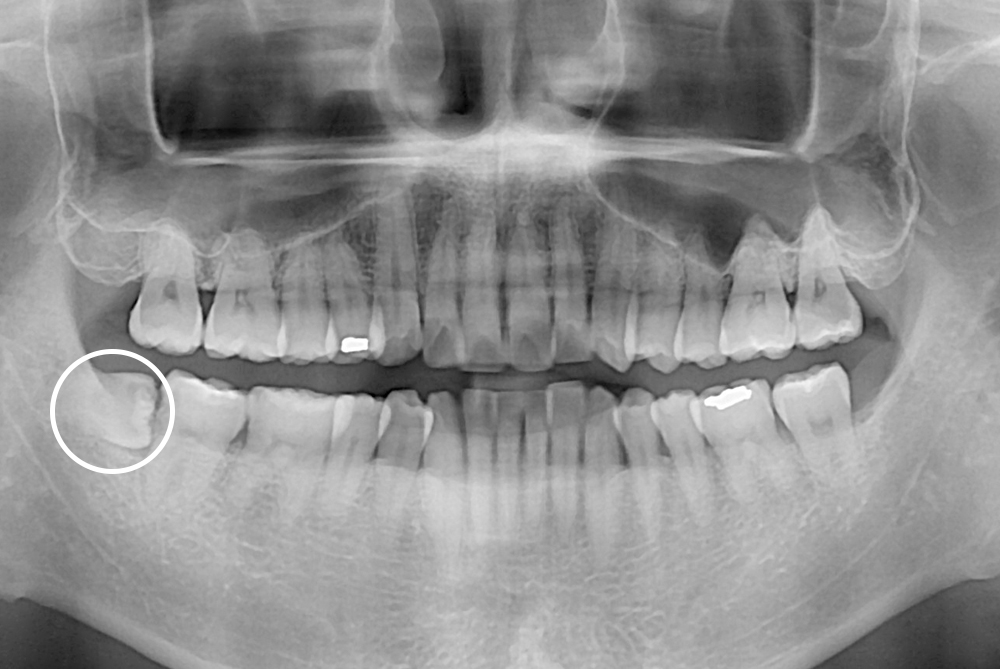

[사랑니] 매복 사랑니 발치

치료후 : 2018-08-16

세종치과는 구강악안면외과학 박사이신 원장님이 발치하는 치과입니다.